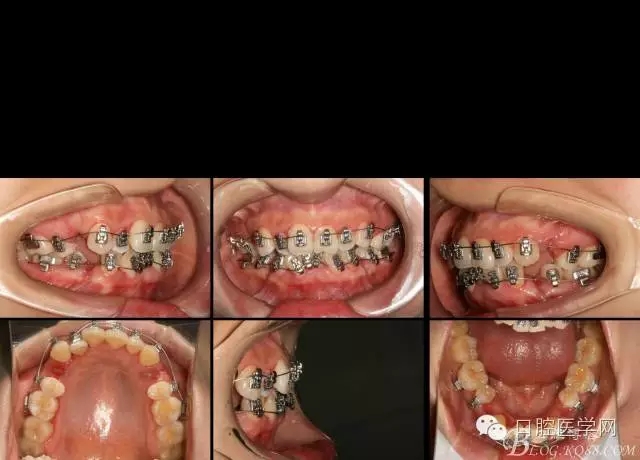

2016.3.3初裝矯正器,014Tn絲激活牙齒,利用交互支抗初步排齊前牙,為主弓絲置入創(chuàng)造更好條件。

2016.4.8 第一次復(fù)診,換為022*016tn扁絲,在上下尖牙遠(yuǎn)中用等力拉簧滑動(dòng)關(guān)閉,內(nèi)收前牙。